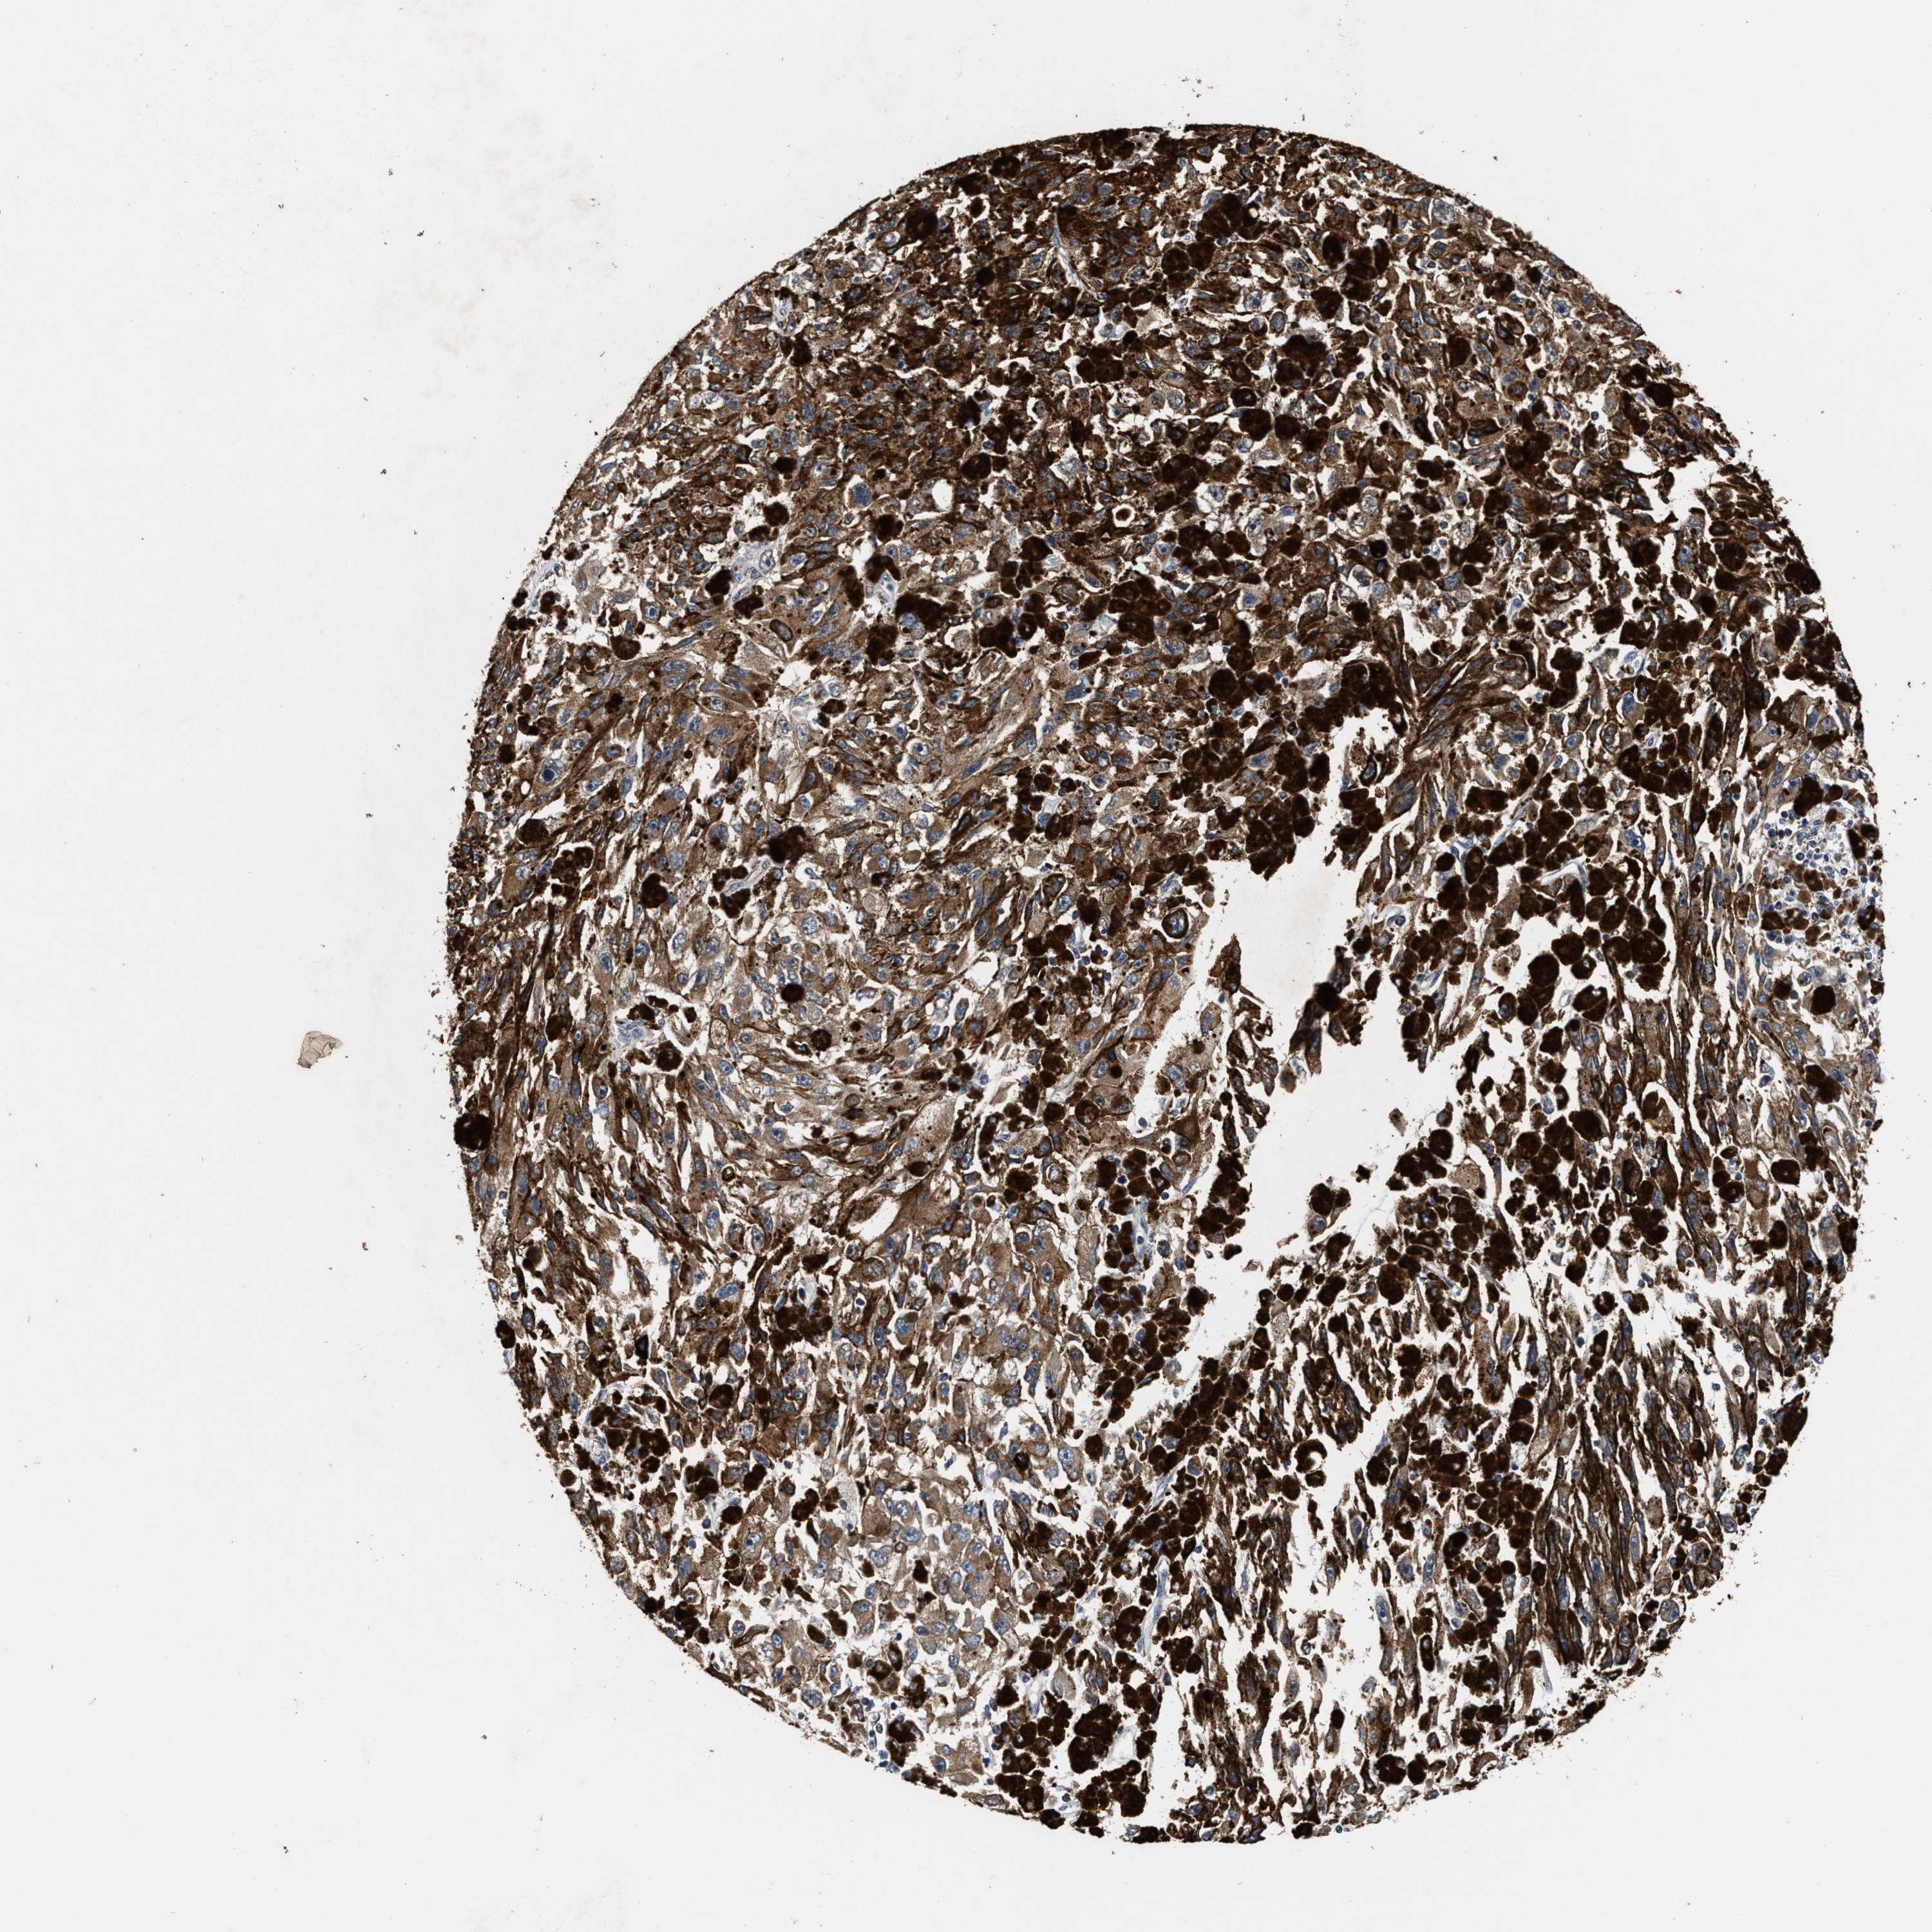

MELANOMA - Protein expressioni

A mouse-over function shows sample information and annotation data. Click on an image to view it in a full screen mode. Samples can be filtered based on level of antibody staining by selecting one or several of the following categories: high, medium, low and not detected. The assay and annotation is described here.

Note that samples used for immunohistochemistry by the Human Protein Atlas do not correspond to samples in the TCGA dataset.

Antibody stainingi

Antibody staining in the annotated cell types in the current human tissue is reported as not detected, low, medium, or high, based on conventional immunohistochemistry profiling in selected tissues. This score is based on the combination of the staining intensity and fraction of stained cells.

Each image is clickable and will lead to virtual microscopy that enables deeper exploration of all samples and also displays staining intensity scores, fraction scores and subcellular localization as well as patient and tissue information for each sample.

HPA022434

HPA022953

HPA022959

HPA028758

CAB007783

Malignant melanoma, NOS

Malignant melanoma, Metastatic site